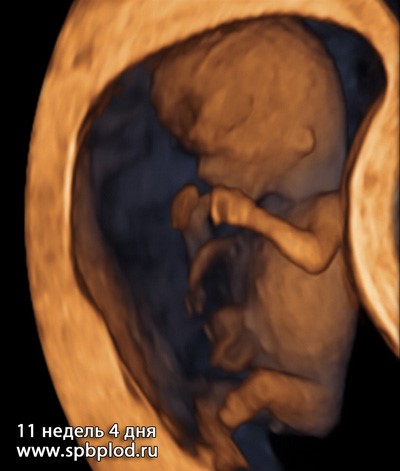

А так выглядит плод на объемных изображениях (3D/4D УЗИ) в первом триместре:

3D УЗИ пплода в 11 недель и 4 дня